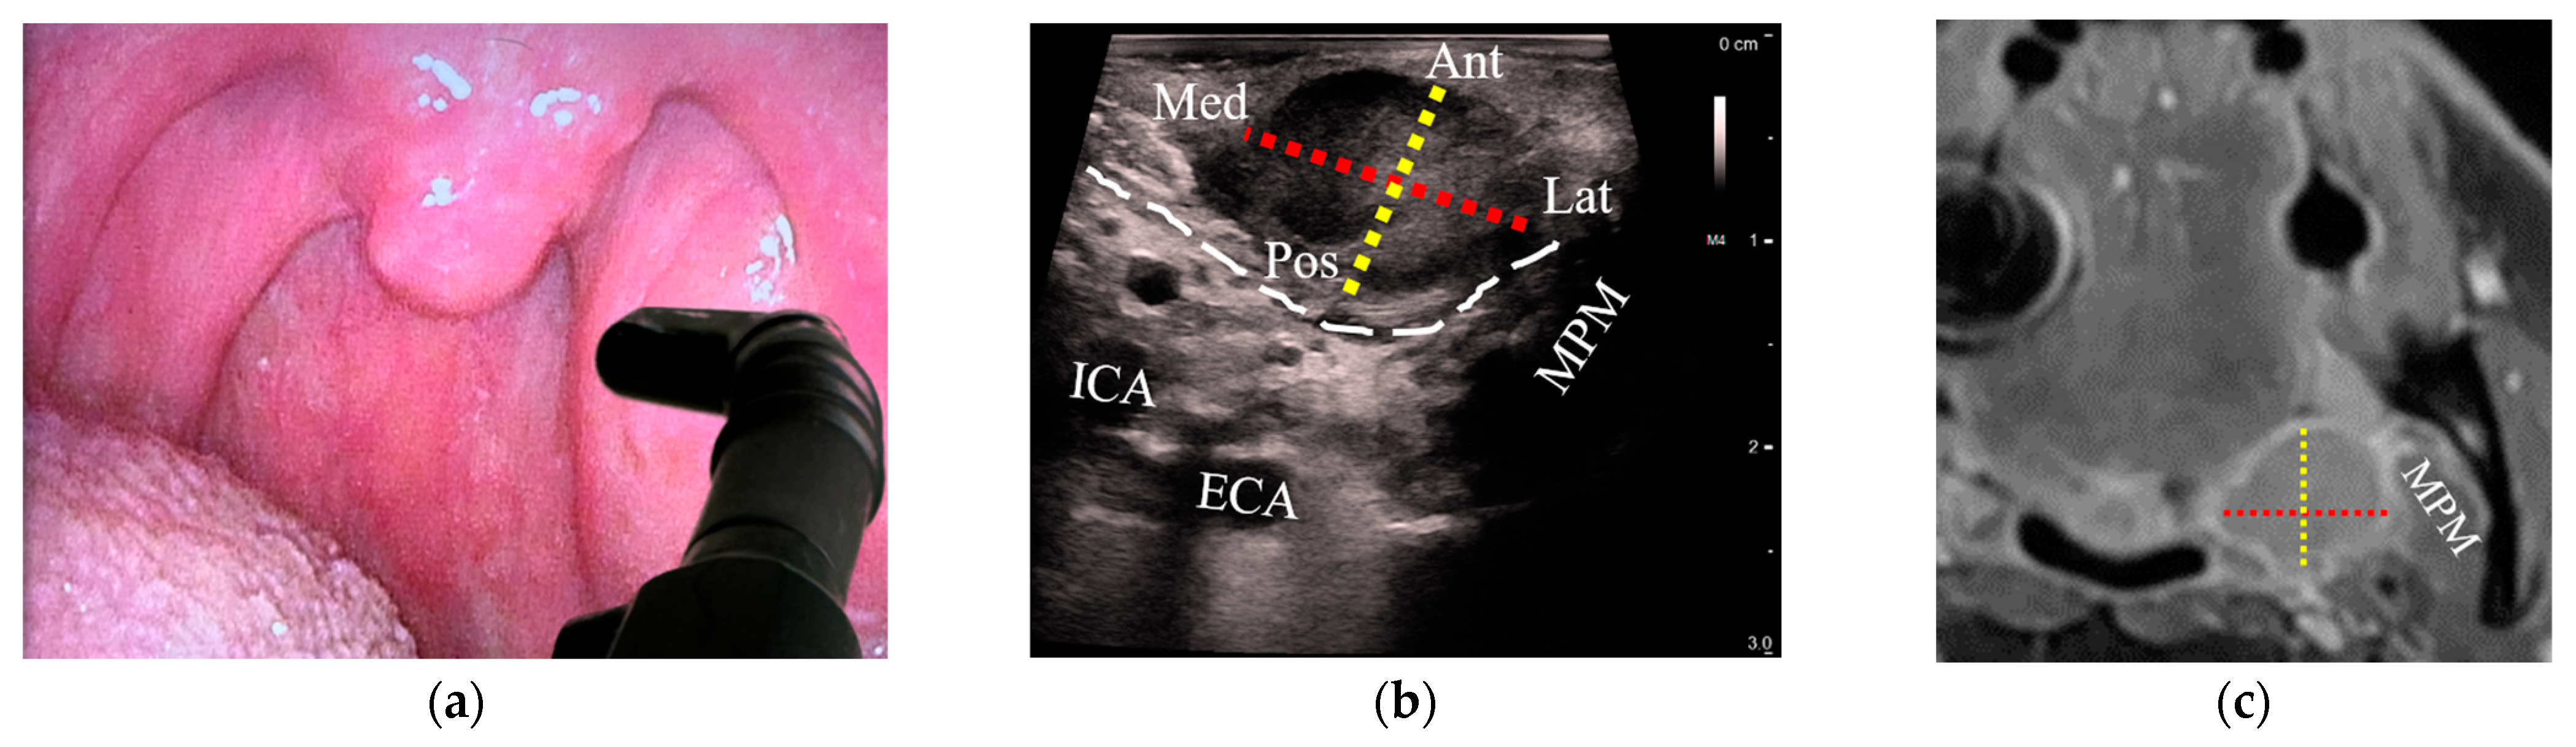

Tumor size was estimated with both US and MRI in 18/21 patients with OPCs (86%); three patients whose tumors could not be delineated on US were excluded from analysis. In all cases, outpatient US was performed a median of 5 days after MRI (interquartile range: −2 to 10 days). A high correlation between US and MRI was observed when comparing the tumor diameter along the US depth axis, which corresponded to the anteroposterior diameter (R = 0.80, Figure 3a). The lateral US axes corresponding to craniocaudal (R = 0.54) and mediolateral diameters (R = 0.49) demonstrated moderate correlation with MRI (Figure 3b,c). Figure 4 illustrates transoral transducer orientations and the corresponding US axes compared to MRI.

Figure 4.

Comparison of tumor diameters between transoral US and corresponding MRI images of a stage-T2 palatine tonsil HPV+ SCC: (a) a patient with an asymmetric left palatine tonsil with an inserted hockey-stick ultrasound transducer placed onto the tonsil in a transverse plane; (b) transverse US reveals a palatine tonsil tumor. Tumor diameters are represented from medial (Med) to lateral (Lat) with a red dotted line and from anterior (Ant) to posterior (Pos) with a yellow dotted line; (c) axial MRI with the corresponding diameters as in (b, red and yellow dotted lines); (d) transducer oriented in the sagittal plane; (e) sagittal US with the cranial (Cra) to caudal (Cau) diameter added (blue dotted line) along with Ant-Pos (yellow dotted line); (f) sagittal MRI with the corresponding diameters as in (e, blue and yellow dotted lines). US: ultrasound; MRI: magnetic resonance imaging; HPV+ SCC: human papillomavirus-positive squamous cell carcinoma; ICA: internal carotid artery; ECA: external carotid artery; MPM: medial pterygoid muscle; SPM: stylopharyngeus muscle; white dashed line: constrictor muscle; Ant: anterior; Pos: posterior; Med: medial; Lat: lateral; Cra: cranial; Cau: caudal.